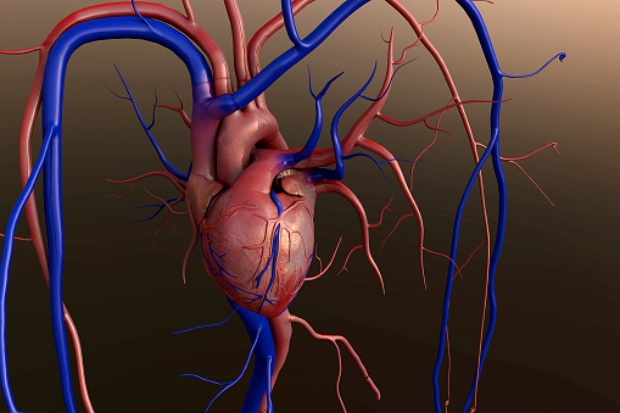

Understanding broken heart syndrome: Causes, symptoms, and treatment

Can you die from a broken heart? Researchers and heart experts suggest that broken heart syndrome is a real thing. A broken heart can do more than just cause emotional distress – it can actually compromise your heart health and cause real heart problems. In fact, a broken heart brought on by an emotional stressor ...click here to read more